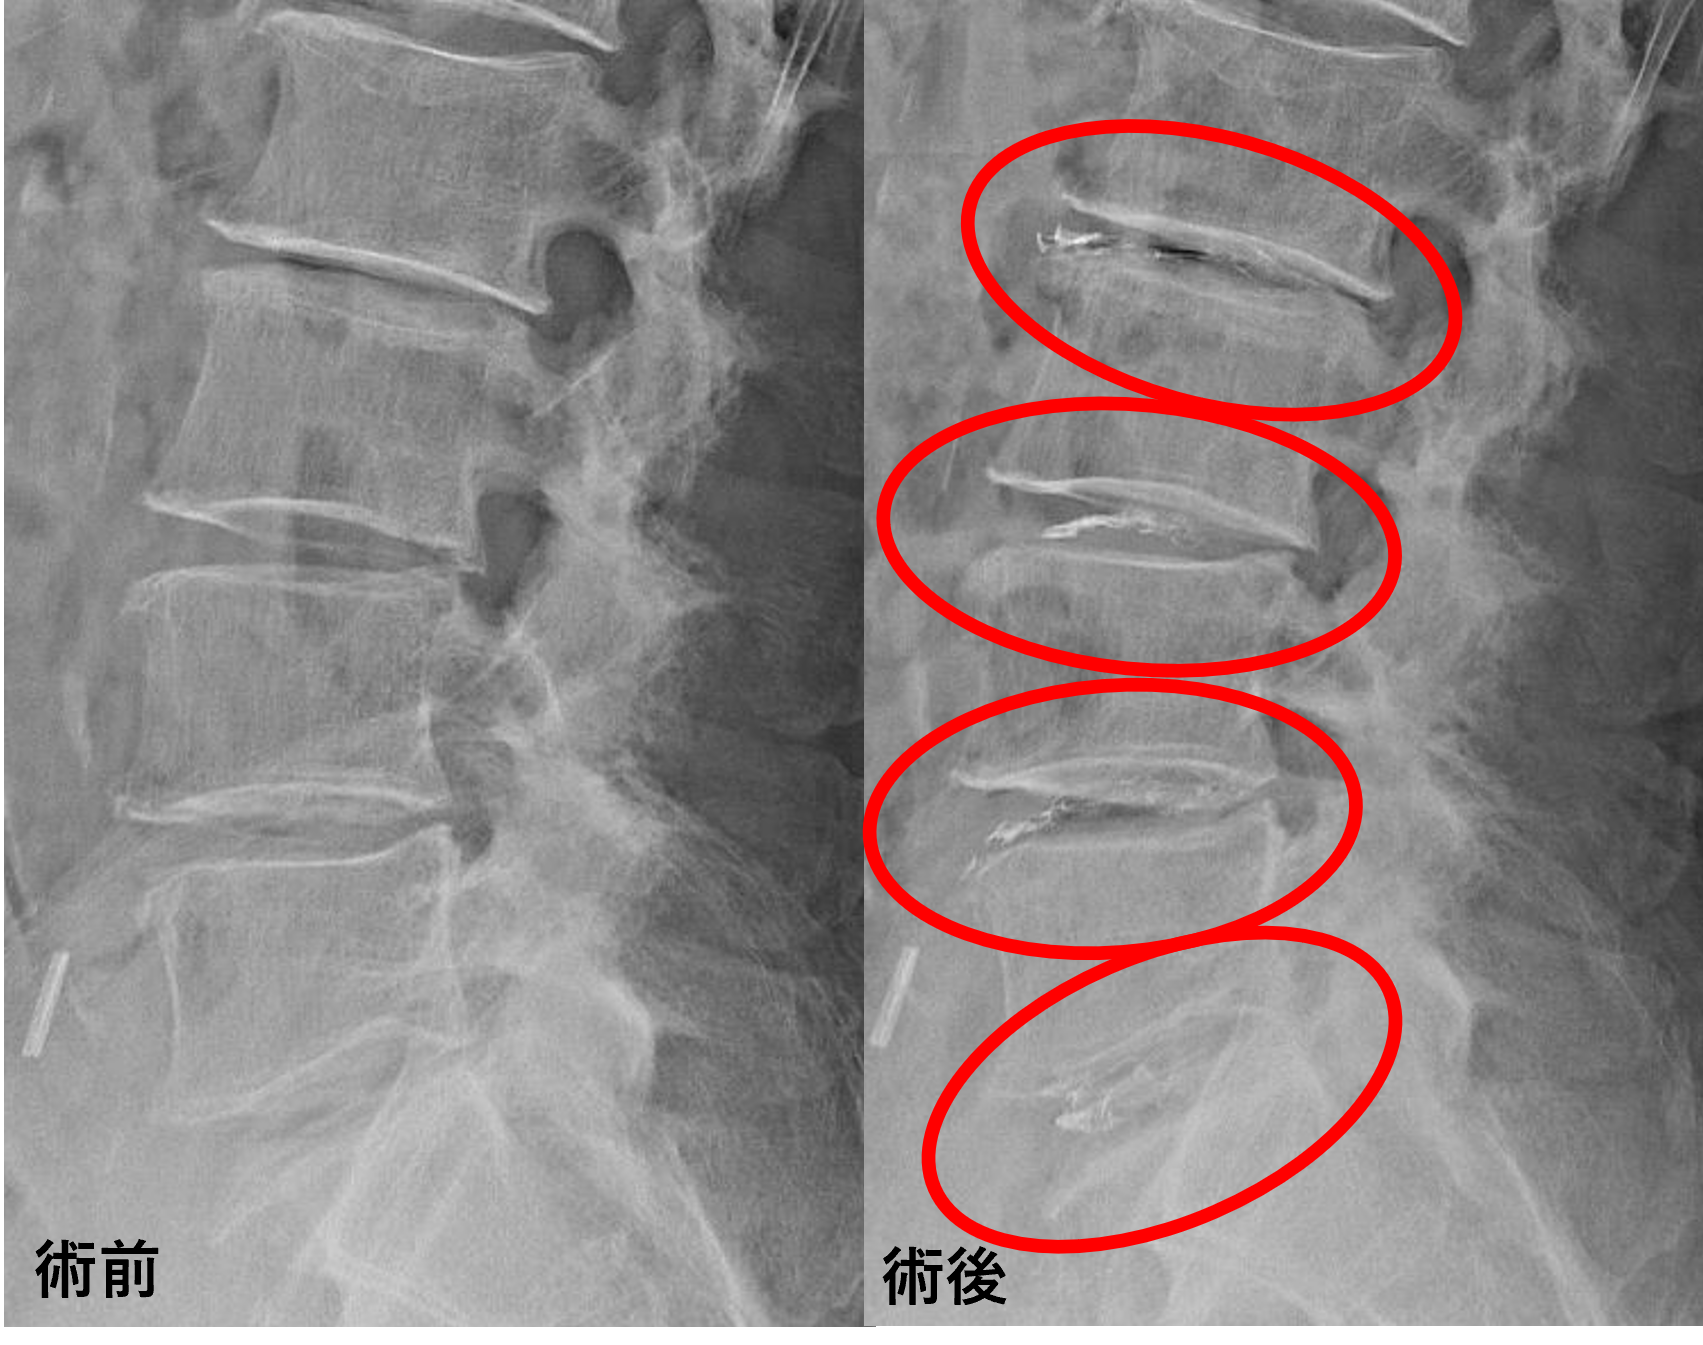

画像及び所見について

• L1/2 – 椎間板変性、膨隆、軽度椎間孔狭窄

• L2/3、3/4、4/5 – 椎間板変性、膨隆、椎間孔狭窄、脊柱管狭窄

• L5/s – 椎間板変性、膨隆、椎間孔狭窄

以上のことが画像上認められました。

L2/3、3/4、4/5、5/sの椎間板所見による脊柱管の圧排が、症状の原因の可能性が高い。

患者様と相談の元、L2/3、3/4、4/5、5/sにセルゲル法を施行